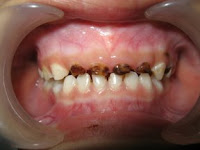

hallo bloggers… anda terganggu dengan gigi si kecil yang hitam-hitam seperti ini?

pertama-tama jaringan karies yang kehitam-hitaman

akan dibersihkan dahulu…